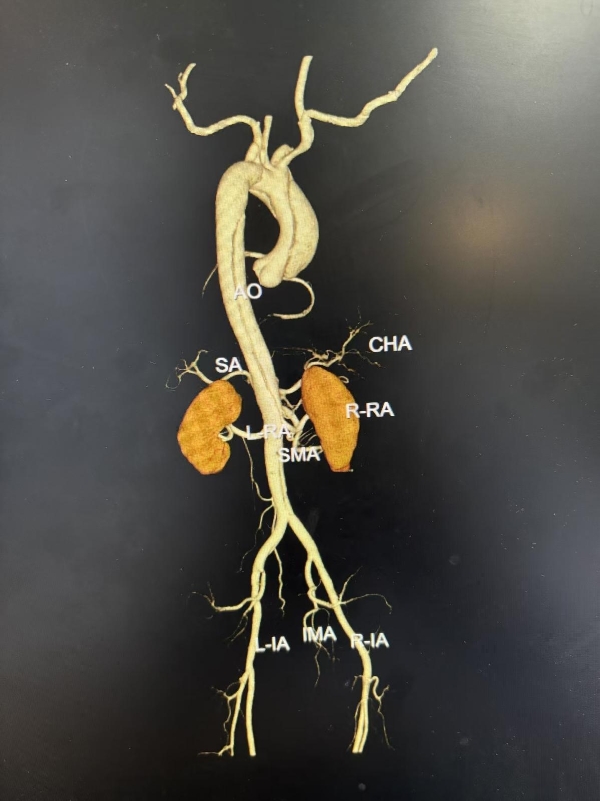

52岁的刘先生,因“突发胸痛2小时”就诊于外院,诊断为急性主动脉夹层(Stanford A型),累及无名动脉、左颈总动脉、左锁骨下动脉等多个分支血管,病情及其危重,需要立即急诊手术。由于该病情重、手术难度大、手术风险极高,对手术医生技术要求非常高,能做该类手术的医院屈指可数。当地医院不能开展如此高难度的顶级手术,建议立即转院,遂慕名来到交大二附院心血管病院急诊就诊。病情紧急,时间就是生命,高峰主任第一时间组织多学科会诊,并开通紧急绿色救治通道,仅用一个小时即完成了术前准备,成功为患者实施了高难度的深低温停循环下主动脉窦部成形+升主动脉、主动脉全弓置换+术中象鼻支架植入术,帮助患者重建生命通道。整个手术犹如刀尖上的舞蹈,开胸、游离血管、建体外循环、切除病变血管、置换人工血管、吻合、植入支架,每一步都小心翼翼。凭借过硬的技术水平和手术团队的密切配合,历经7个多小时,顺利拆除患者体内的“定时炸弹”,使患者转危为安。